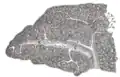

Coupe transversale de la rate, montrant le tissu trabéculaire et la veine splénique ainsi que ses affluents.

Coupe transversale de la rate humaine, montrant la disposition de l'artère splénique et de ses branches.

Coupe de la rate, montrant les terminaisons des petits vaisseaux sanguins.